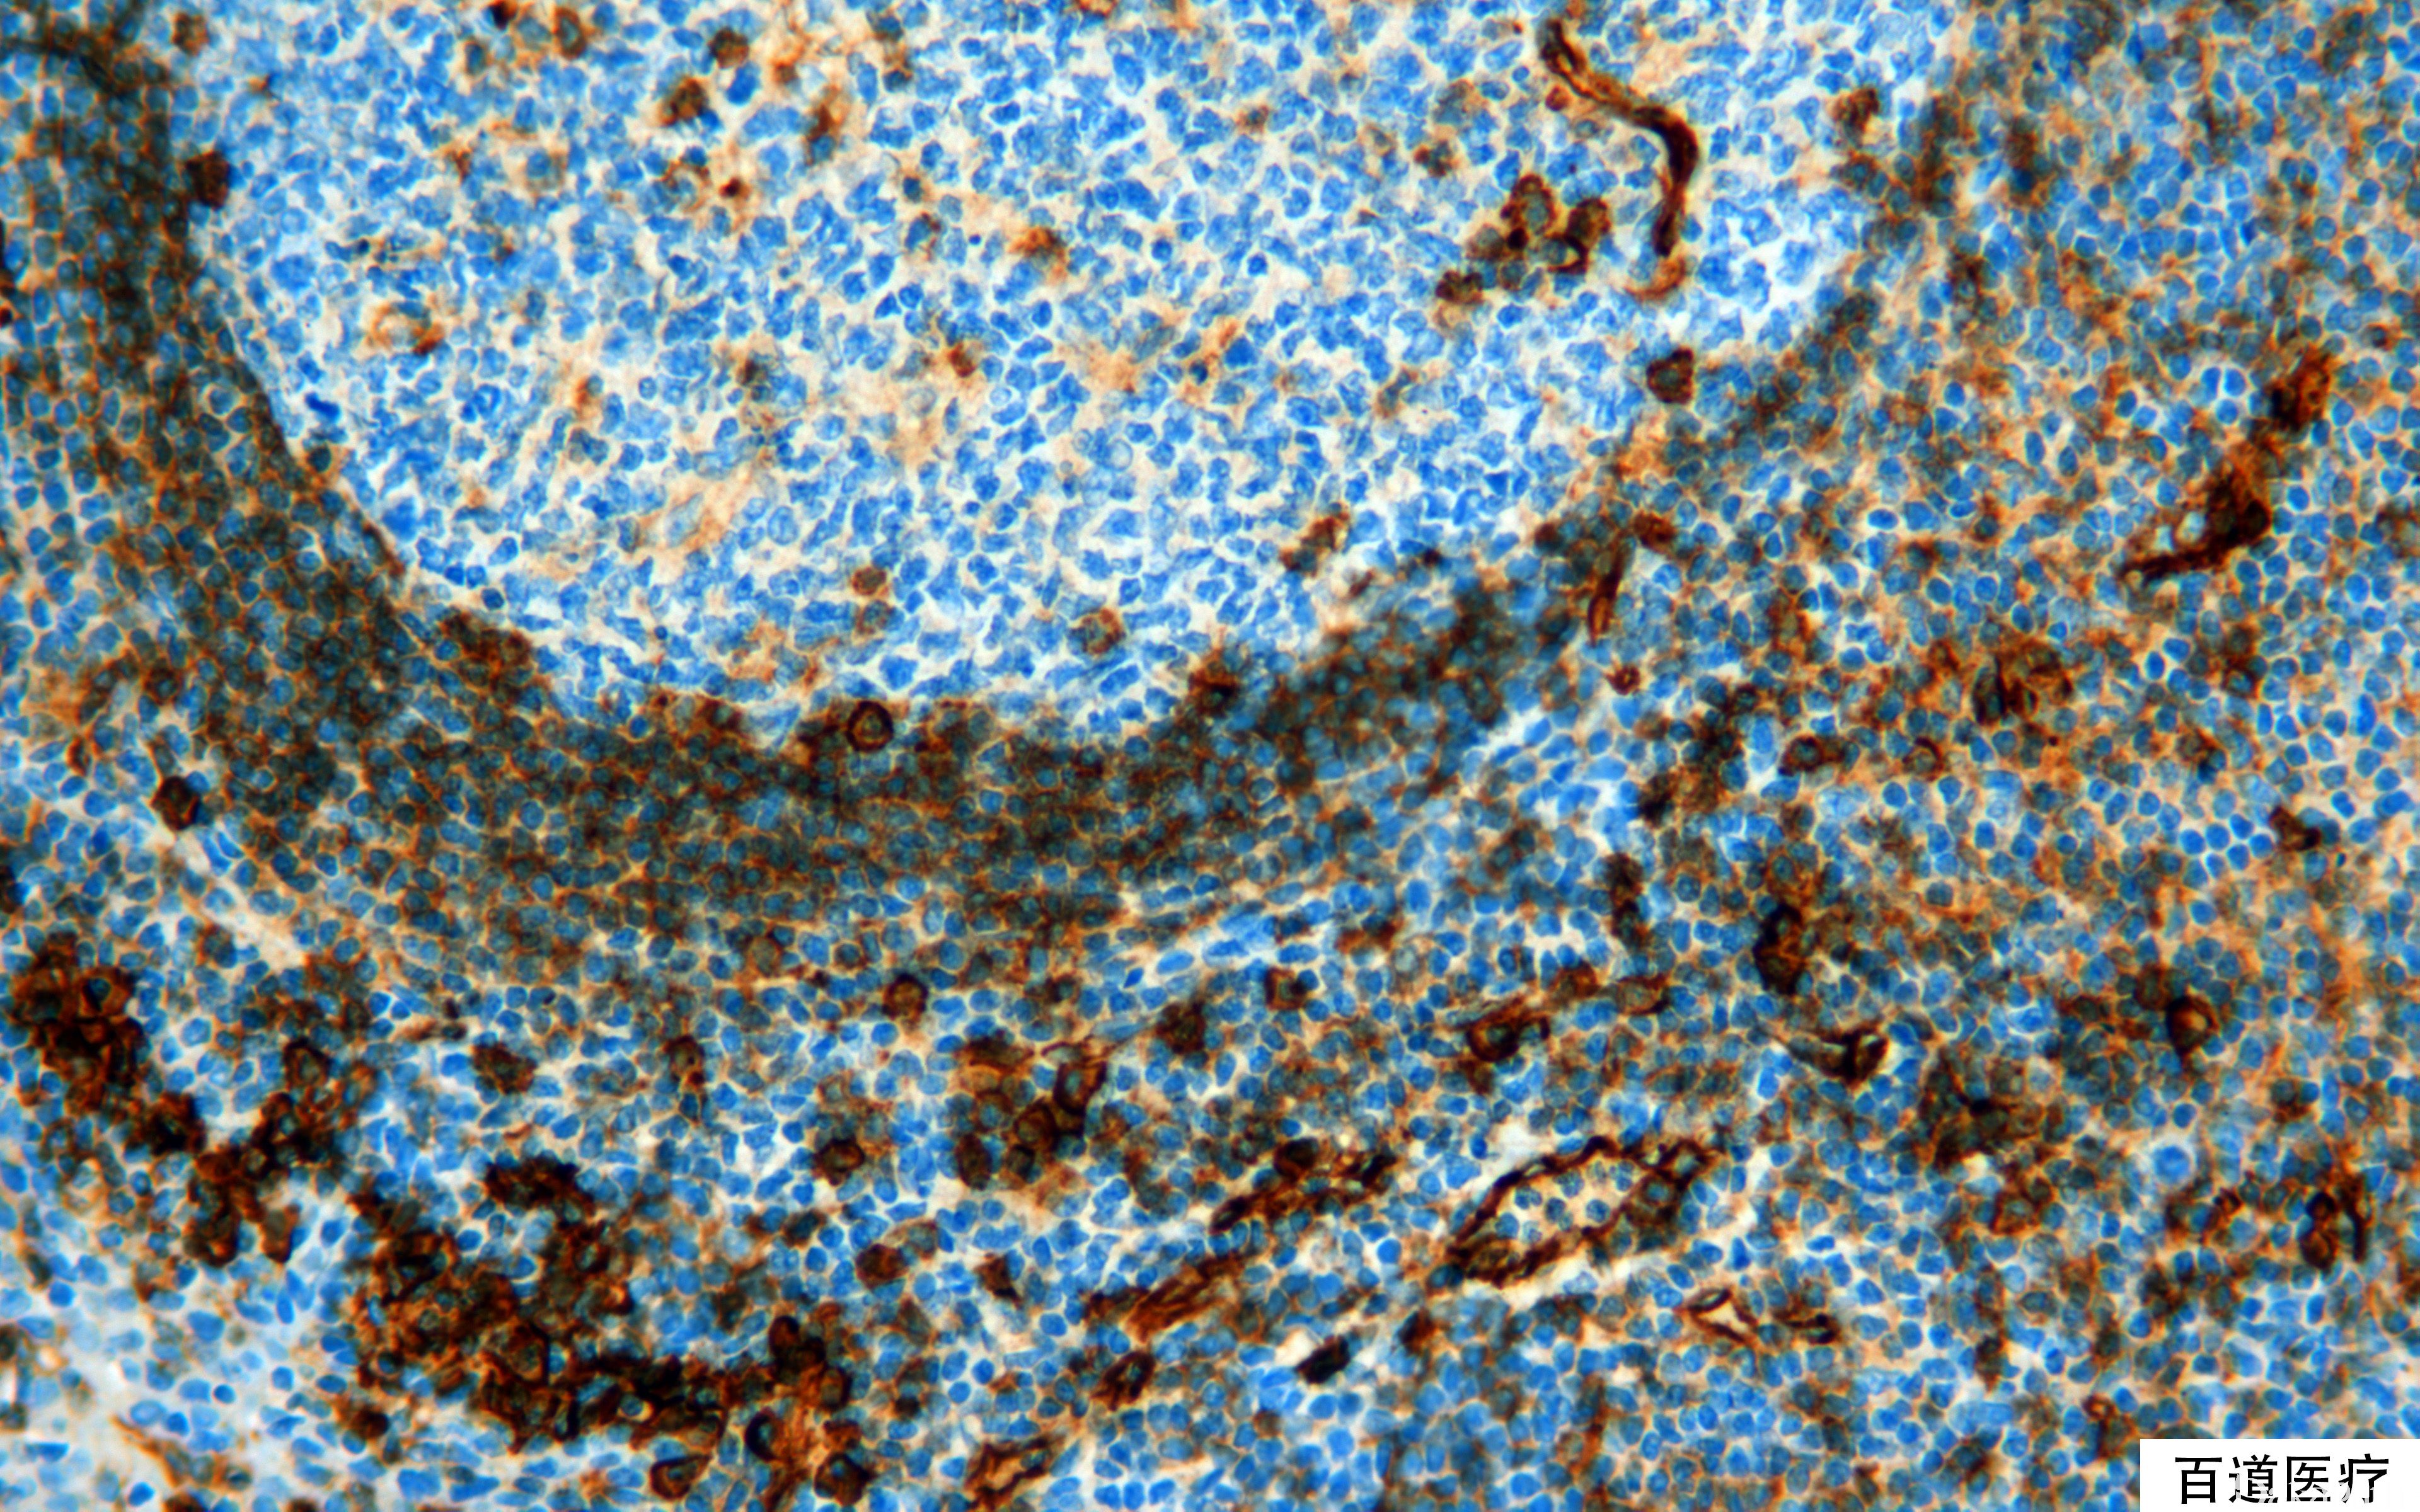

CD31

别名: PECAM-1

血小板内皮细胞黏附分子,是一种膜糖蛋白。属免疫球蛋白超家族,在所有连续性内皮表达,但不连续的血窦内皮不表达。巨核细胞、血小板、髓细胞、NK 细胞和部分 T、B 细胞也表达。

血管内皮细胞肿瘤的诊断与鉴别诊断(比 CD34、VIII 因子更敏感、更特异)。